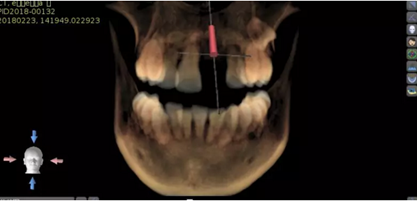

2.術(shù)前植體設(shè)計(jì)

3.術(shù)前導(dǎo)板設(shè)計(jì)